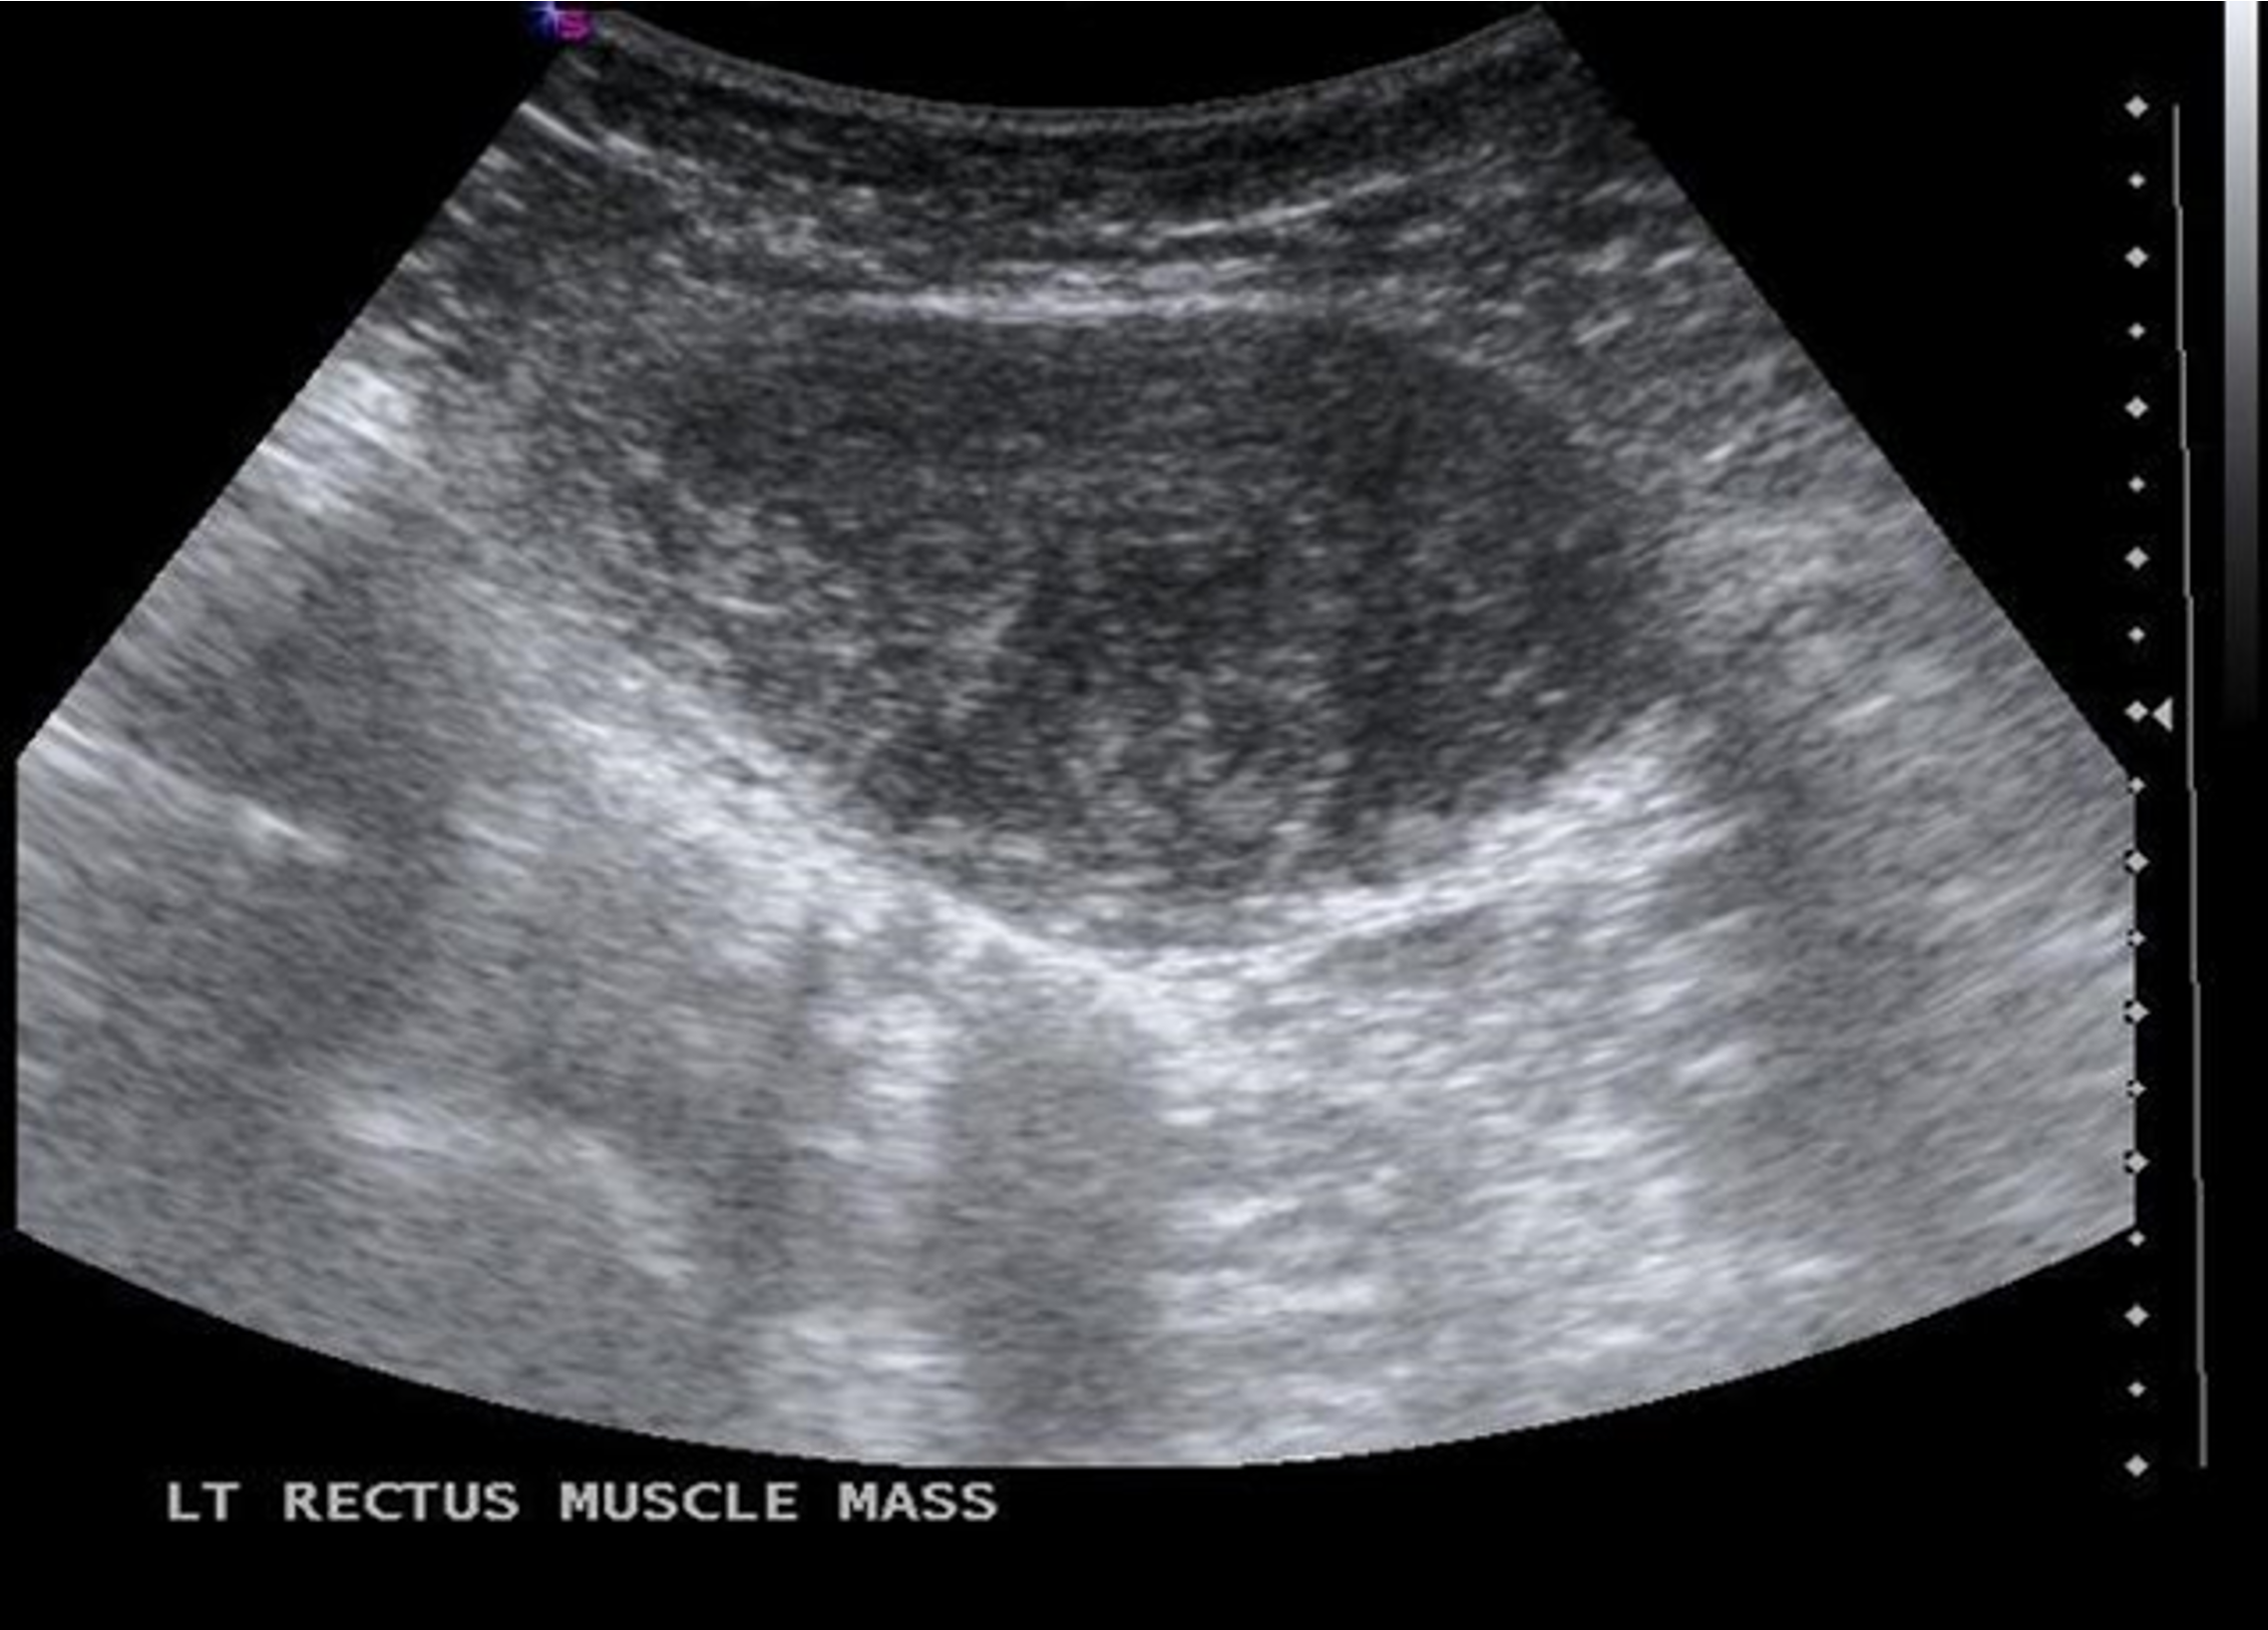

- Fibromatosis/ neoplasm: from fibroaponeurotic part of rectus abdominis.

- Diagnosis: CT or MRI for delineation, core needle biopsy.